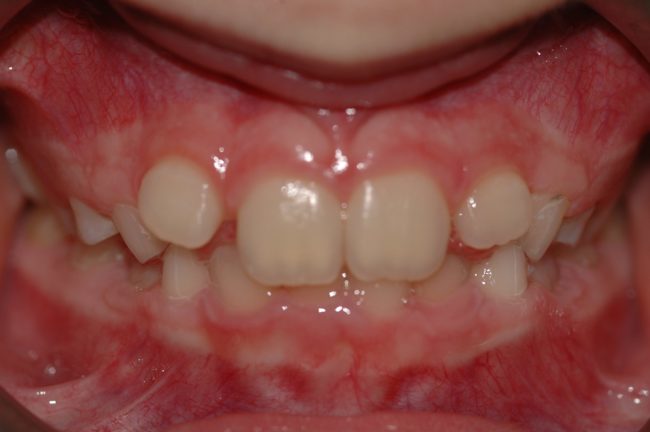

Un caso di anomalia di formazione radicolare

Diverse sono le anomalie che incontriamo nel nostro percorso lavorativo, ma la mancata formazione della radice di un elemento dentale, è cosa abbastanza inaspettata. In questa breve presentazione voglio condividere la mia scelta terapeutica per essere di aiuto a chi si dovesse trovare nella mia stessa situazione e per stimolare ulteriori proposte terapeutiche. Voi come…